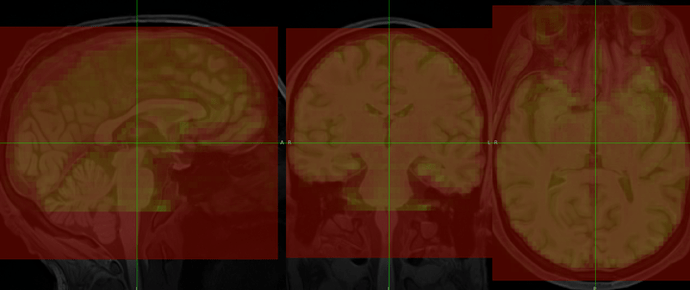

This image shows the “original” BOLD image before any T1 alignment, and as you can see it’s pretty far from the T1’s FOV, but not terribly crooked or rotated, so I expected the registration to turn out better than it has.